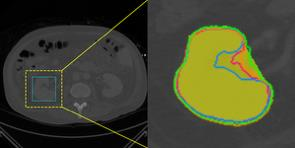

Accurate magnetic resonance imaging (MRI) segmentation is crucial for clinical decision-making, but remains labor-intensive when performed manually. Convolutional neural network (CNN)-based methods can be accurate and efficient, but often generalize poorly to MRI's variable contrast, intensity inhomogeneity, and protocols. Although the transformer-based Segment Anything Model (SAM) has demonstrated remarkable generalizability in natural images, existing adaptations often treat MRI as another imaging modality, overlooking these modality-specific challenges. We present SAMRI, an MRI-specialized SAM trained and validated on 1.1 million labeled MR slices spanning whole-body organs and pathologies. We demonstrate that SAM can be effectively adapted to MRI by simply fine-tuning its mask decoder using a two-stage strategy, reducing training time by 94% and trainable parameters by 96% versus full-model retraining. Across diverse MRI segmentation tasks, SAMRI achieves a mean Dice of 0.87, delivering state-of-the-art accuracy across anatomical regions and robust generalization on unseen structures, particularly small and clinically important structures.